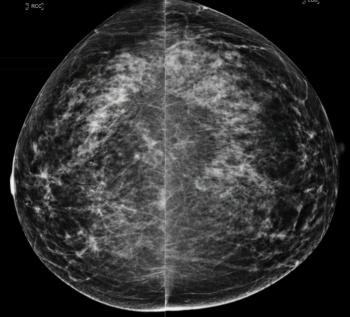

Figure 1. Images in a 55-year-old screening participant. (a, b) Normal digital full-field mediolateral oblique (a) and craniocaudal (b) mammograms (BI-RADS category 1) show a heterogeneously dense breast (ACR category C). (c) Screening ultrasound image shows normal findings (BI-RADS category 1). (d) MR-guided biopsy enabled us to confirm the presence of an invasive high-grade triple-negative cancer (no special type [NST], pT1b, N0, M0). (d) Breast MR image shows a suspicious enhancing mass (arrow) in the left breast (BI-RADS category 5).E

Figure 3. Normal digital full-field mediolateral oblique mammogram (BI-RADS category 1) show a heterogeneously dense breast (ACR category C).

Figure 4. Normal digital full-field craniocaudal mammogram (BI-RADS category 1) show a heterogeneously dense breast (ACR category C).